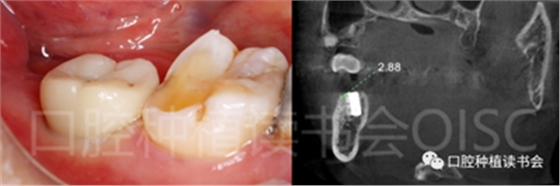

術前CBCT(美亞光電)檢查:47根分叉下方骨高度及骨寬度滿足即刻種植要求(圖13)。

圖13 47根分叉區(qū)骨寬度及骨高度(與下頜神經(jīng)管之間的距離)滿足即刻種植要求。

5.4.4 種植冠封閉螺絲孔后,調(diào)合,拋光,完成最終修復(圖27);戴牙前CBCT顯示:種植體頰側(cè)骨板厚度為2.88mm;47種植冠獲得了良好的穿齦輪廓,并維持了正常的頰側(cè)牙弓輪廓。